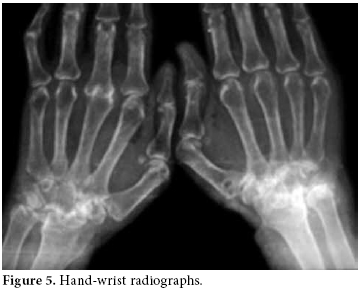

The RA disease activity score (DAS) was calculated as 6.14. Predominant findings in hand X-rays were symmetric joint erosions in carpal bones along with ankylosis leading to contracture, joint space narrowing, cystic changes, and periarticular osteoporosis (figure 5).